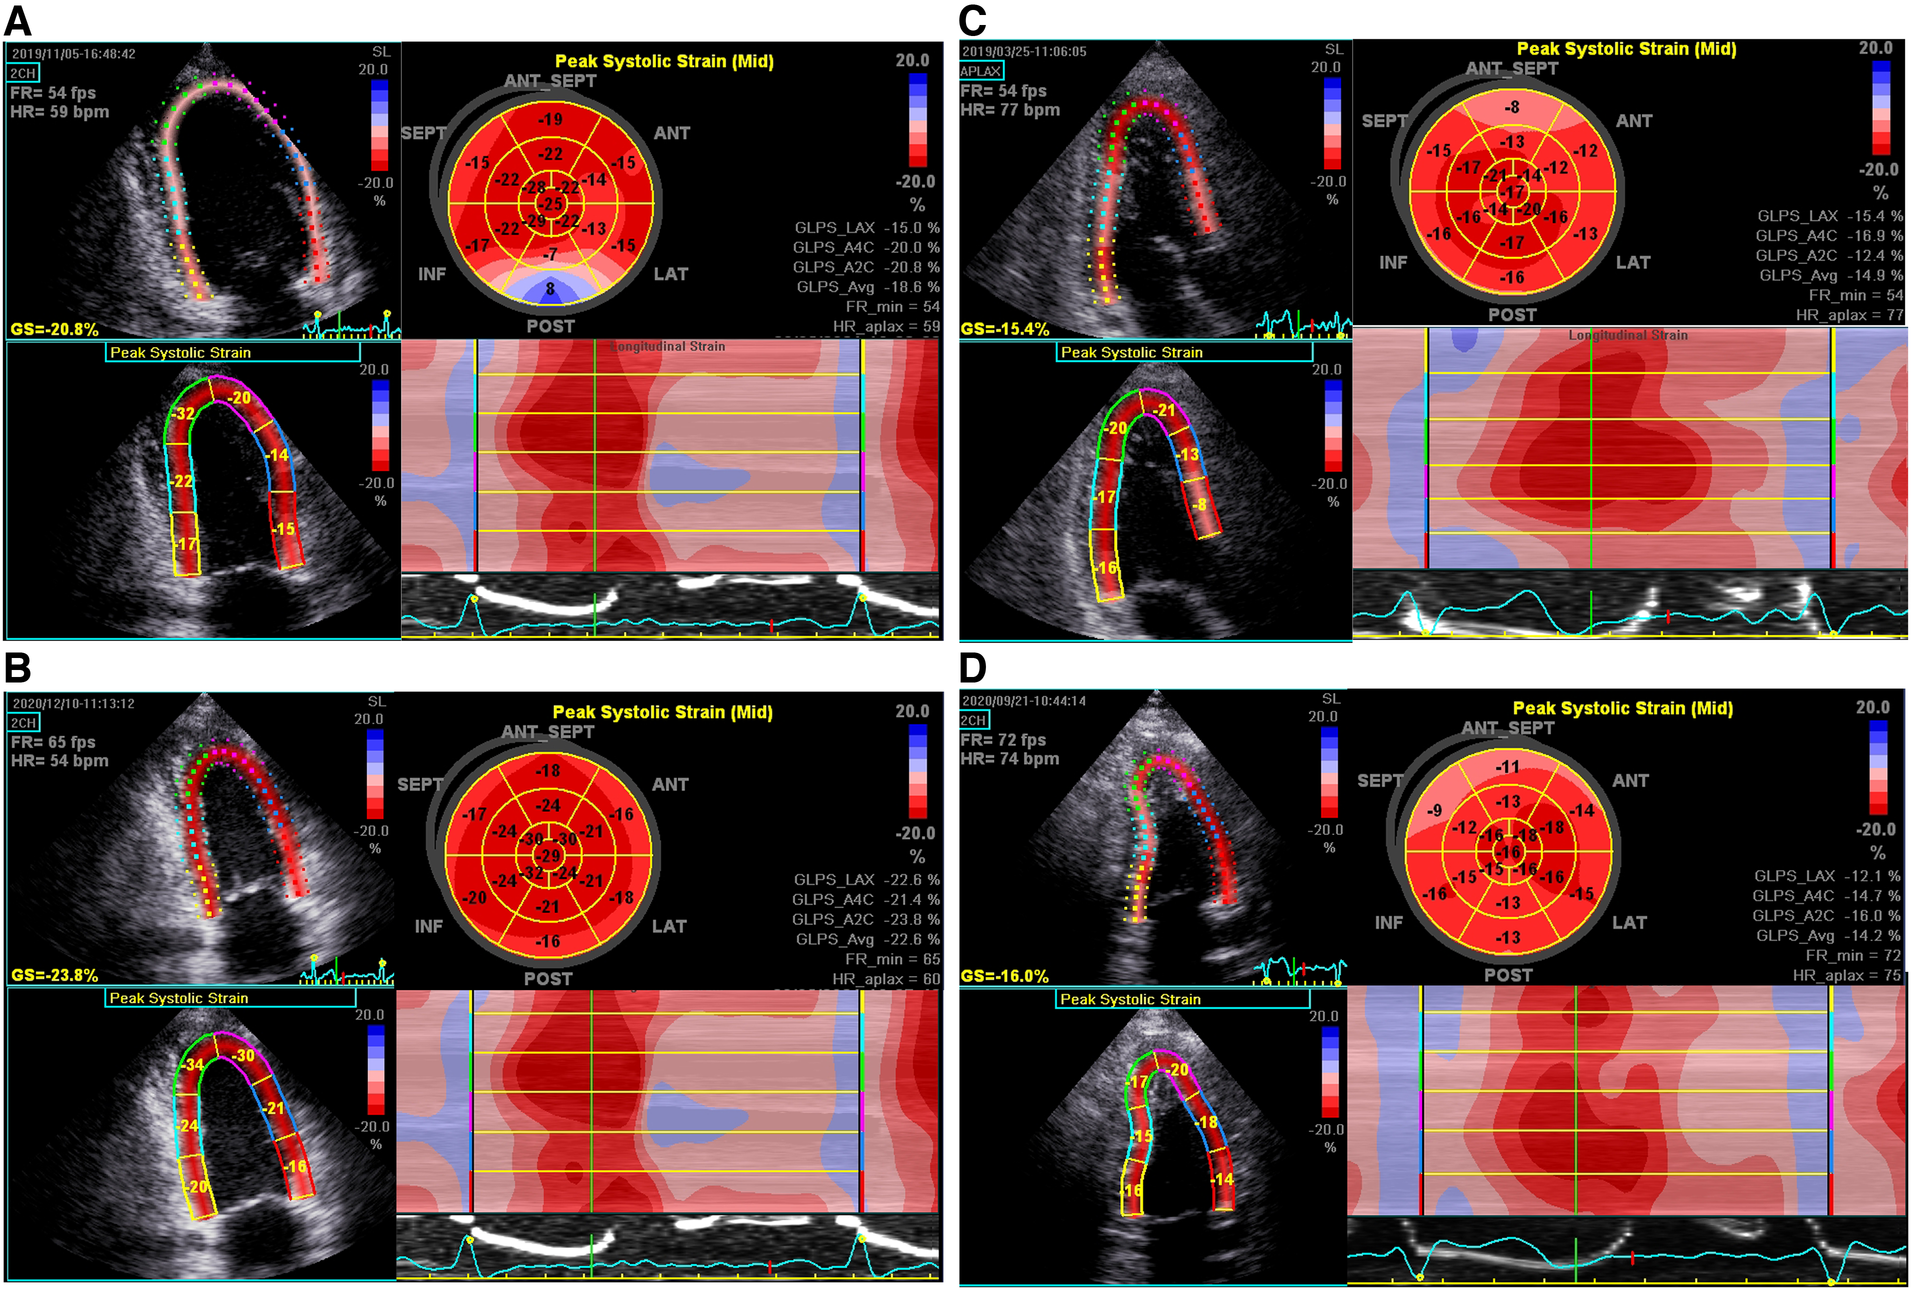

Global longitudinal strain (GLS) was obtained by two-dimensional (2D) speckle tracking echocardiography (STE). The 2D gray scale images of three consecutive cardiac cycles for each of the apical two-chamber, three-chamber, and four-chamber views at end-systole were saved for strain analysis. Data processing was conducted offline by using Echo Pac (version: 113, 2017; GE Vingmed, Horten, Norway). GLS was quantified by automated functional imaging analysis, based on the AHA 17-segment LV model, expressed as the absolute value of the mean. Representative images of “bull’s-eye” of two FM patients with different LGE mass% were showed in Figure 2.

Figure 2. Representative bull's-eye displays of GLSs in a 30-year-old man (A,B) and a 39-year-old man (C,D) with FM, respectively, upon discharge and 2-year follow-up. (A) Significant reduction of PSLSs in basal-, mid-inferior, posterior, and antero-septal segments, with the average GLS being 18.6%; (B) complete normalization of GLS; (C) significant reduction of PSLSs in basal-, mid-, apical-inferior, posterior and antero-septal segments at discharge, with the average GLS being 14.9%; (D) the GLS remained at 14.2%.